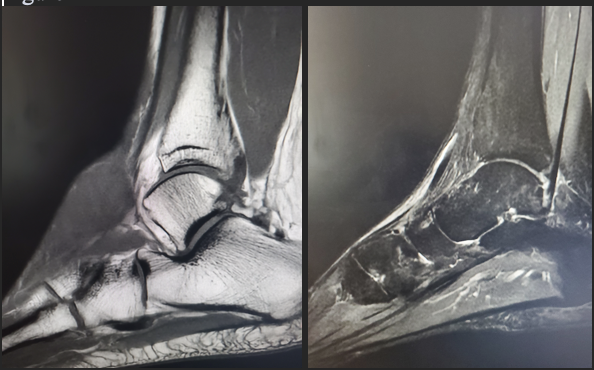

Magnetic resonance imaging (MRI) of the left foot and ankle indicated the presence of a heterogeneously enhancing cystic and solid mass positioned anterior to the talus and navicular bones. The mass, measuring approximately 3.7 x 2.3 x 2.8 cm, exhibited an ill-defined boundary and showed no osseous involvement (Figure 1). The radiologist performing the initial read included hemangioma in the differential diagnosis.